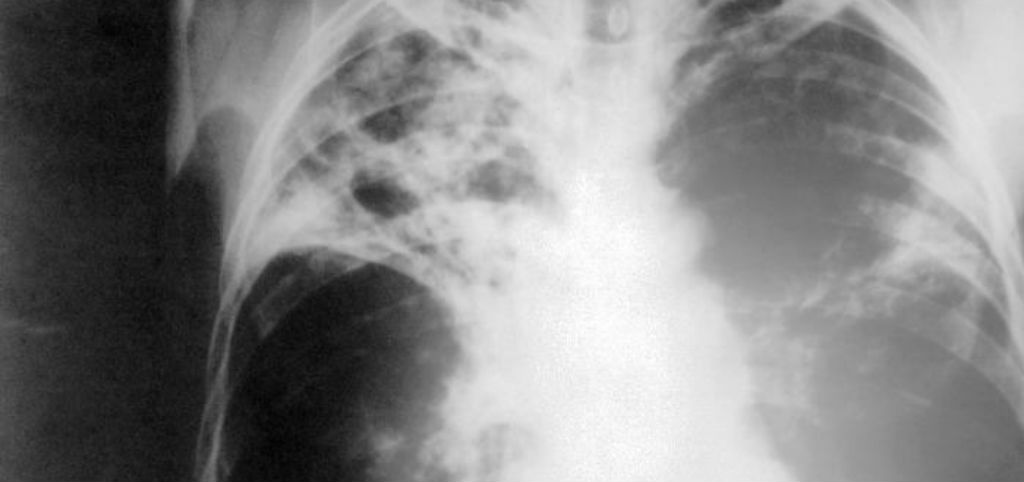

Foto: CDC